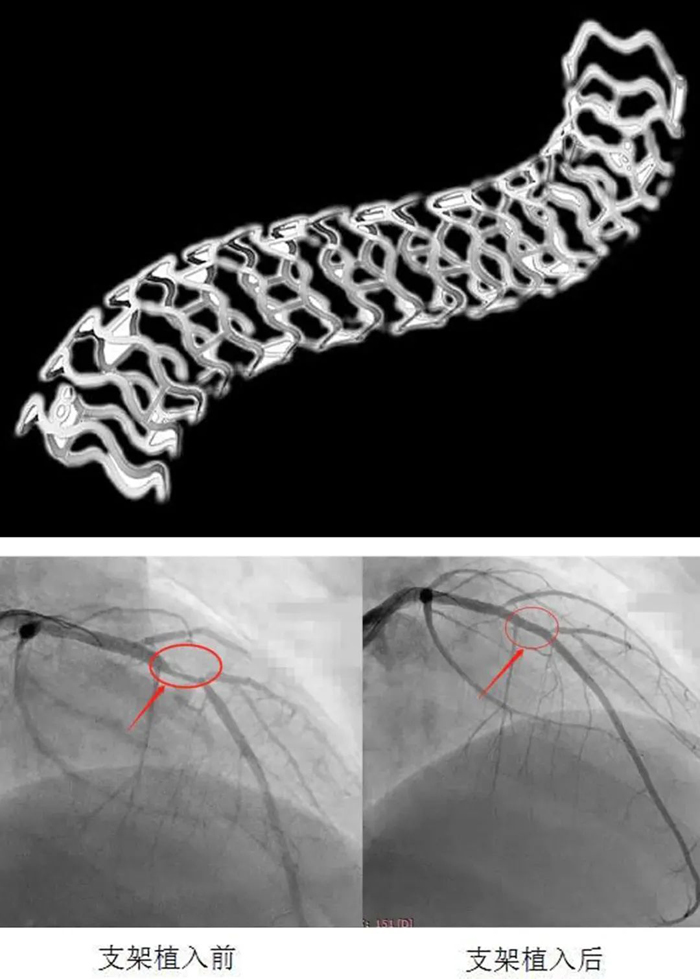

患者入院后完善術(shù)前準(zhǔn)備,給予冠脈造影檢查示:右冠脈支架通暢,未見(jiàn)狹窄,左冠脈前降支近端可見(jiàn)90%局限性狹窄。考慮患者年輕,病變?yōu)锳型病變,參考患者家人意愿,決定給予患者可降解支架植入。

在郭明主任指導(dǎo)下,心內(nèi)科介入團(tuán)隊(duì)先對(duì)病變處給予普通球囊及切割球囊充分預(yù)擴(kuò)張,再給予血管內(nèi)超聲(IVUS)精確測(cè)量血管內(nèi)徑,選擇3.0×28生物可吸收支架,以8atm×30s釋放支架,再以血管內(nèi)超聲(IVUS)對(duì)支架貼壁情況給予評(píng)估后,以3.0后擴(kuò)球囊給予“修飾”,IVUS再次評(píng)估,貼壁良好,手術(shù)順利結(jié)束。

生物可吸收支架采用完全可降解聚合物材料聚乳酸(PLLA)作為支架基體材料,植入人體后,在三年左右時(shí)間,整個(gè)支架就可以完全降解為水和二氧化碳。與傳統(tǒng)的永久性金屬支架相比,生物可吸收支架在血管內(nèi)可實(shí)現(xiàn)和金屬支架一樣的支撐狹窄血管的功能,可完成對(duì)血管的重塑,并會(huì)逐漸降解,被機(jī)體吸收,患者無(wú)需終身服藥。